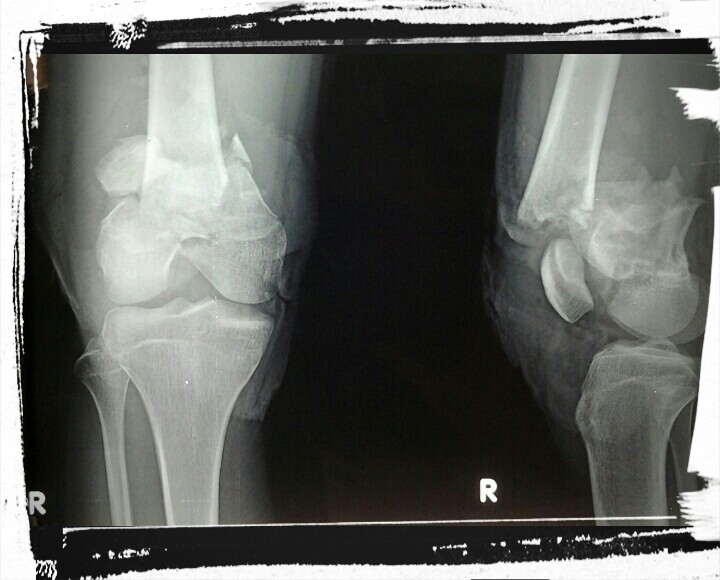

Lelaki dewasa itu tergeletak dengan luka menganga di lutut kanannya, besar sekitar 10 centi dengan tulang menonjol keluar, pecah, dan serat serat otot yg robek tidak beraturan bercampur kerikil, pasir dan potongan rerumput hijau kuning. Darah membasahi celananya yang sengaja digunting oleh petugas. Tidak tampak darah mengalir kencang, bagian ujung kaki teraba hangat dan tidak pucat. Sepertinya pembuluh darah utama kaki kanannya itu aman.

Patah tulang dengan luka terbuka kotor seperti itu hanya salah satu dari sekian hal rutin yang ditemui setiap hari. Patah tulang terbuka dapat menyebabkan infeksi lokal sekitar luka (infected wound) maupun infeksi sistemik (sepsis) . Infeksi sistemik dapat berujung kepada kematian. Infeksi lokal bisa berlanjut lama dan lebih jauh ke dalam tulang, infeksi ini yang disebut sebagai chronic osteomyelitis.

Osteomyelitis kronis termasuk salah satu yang sulit untuk disembuhkan, diperlukan berbagai tindakan termasuk operasi seperti pembersihan (debridemen), membuang nanah yang berada di dalam tulang sekaligus membuang tulang yang mati (sequestrectomy). Bagian jaringan lunak (otot dan sekitarnya) yang terinfeksi dan menjadi jalur keluarnya nanah hingga kulit (sinus track) dibuang. Penanaman cangkok tulang (cancellous bone graft) disertai butir butir antibiotik (antibiotic beads) dilakukan sebagai bagian upaya eradikasi holistik bakteri penyebab osteomyelitis. Sering dijumpai pasien memerlukan berkali-kali operasi disertai pengobatan antibiotik suntik (injeksi) dan minum (oral) dengan jangka lama. Tingkat kambuhan (rekurensi) penderita osteomyelitis cukup tinggi yaitu mencapai 30 %.